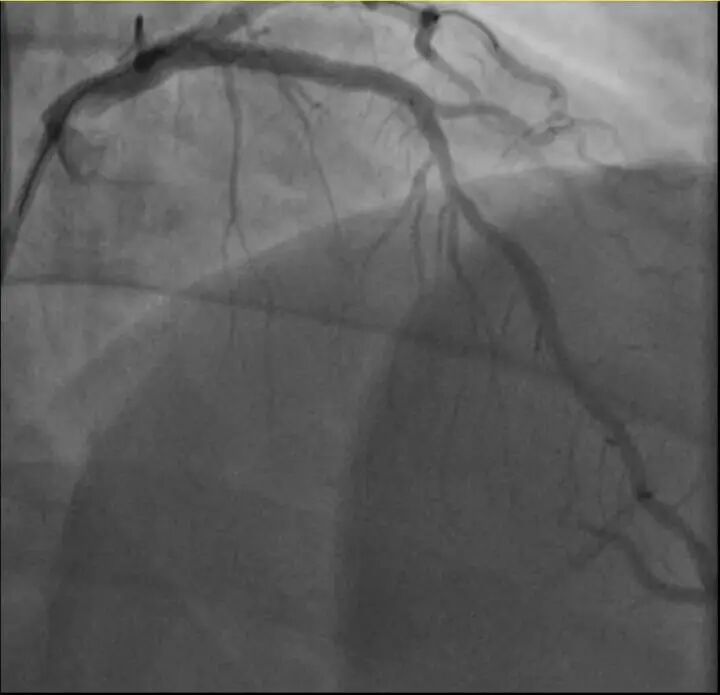

介入治疗前影像图

浙江医院心血管内科的医生分析,剧烈运动导致这位患者心脏的不稳定斑块破裂,进而造成前降支近段次全闭塞。所幸送医及时,孙先生的身体险情被化解。

介入治疗后影像图